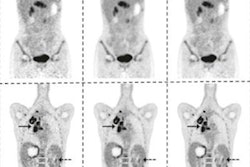

In radiology applications for oral SCC, a convolutional neural network (CNN) was able to predict disease-free survival with 80% accuracy, sensitivity, and specificity from PET images, the researchers reported. Another CNN showed lower performance -- 66.9% sensitivity, 89.7% specificity, and 84% accuracy -- when used on CT for predicting disease-free survival. A deep-learning algorithm also yielded 90% sensitivity for detecting lymph node metastasis from oral SCC on CT.

In addition to providing prognosis predictions, AI could help facilitate personalized treatment from CT images, according to the researchers. One model was 76% accurate for predicting xerostomia, or dry mouth, an adverse effect of radiotherapy caused by toxicity. Another study determined that radiation dose distribution is the most crucial factor for predicting toxicity.